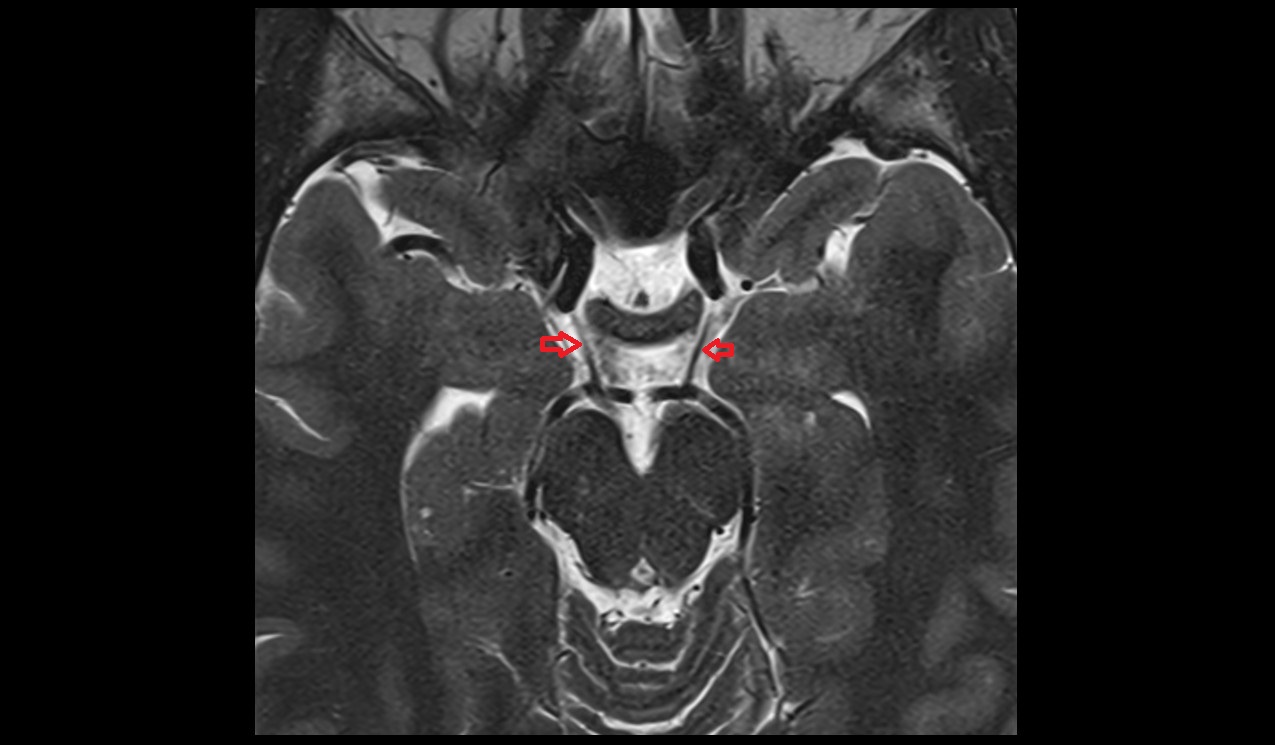

- Hippocampal head

- Head of hippocampus